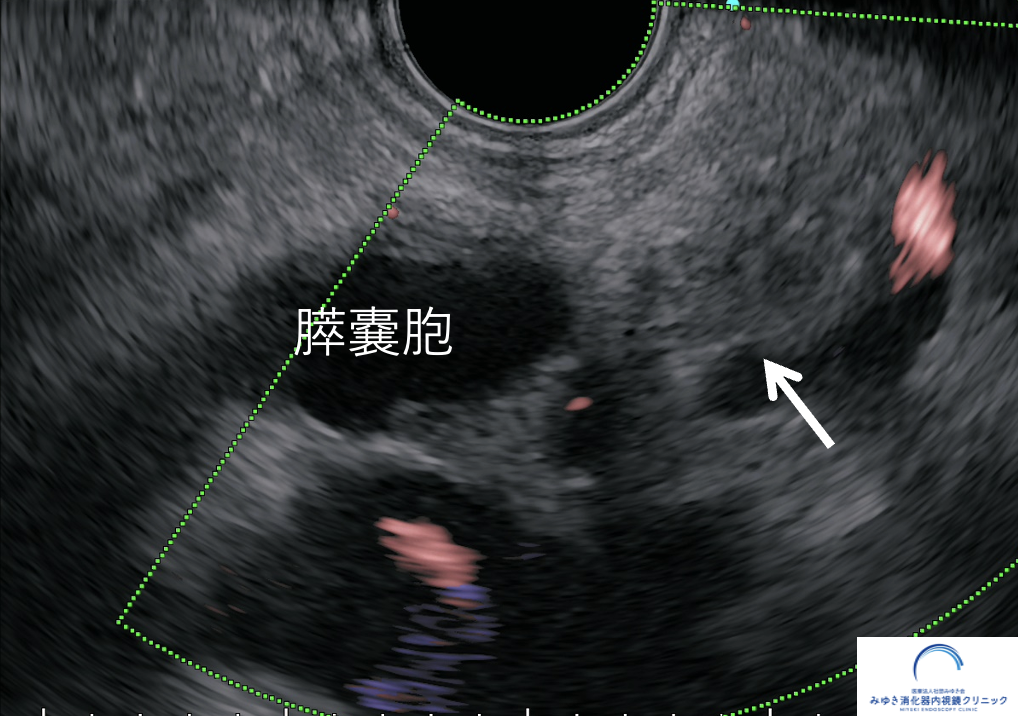

② IPMN(膵管内乳頭粘液性腫瘍)・膵嚢胞

IPMNは、膵管内に粘液を産生する腫瘍性の病変です。 粘液が膵管内にたまることで、膵管が拡張して見えることがあります。

また、IPMNでは膵嚢胞を伴うことが多く、膵管の太さ、嚢胞の大きさ、壁在結節の有無などを確認しながら、 経過観察や追加検査の必要性を判断します。

✓ 膵嚢胞やIPMNを伴っている場合

当院で行っている膵管拡張・膵嚢胞に対するEUS評価

膵嚢胞(IPMN)や膵管拡張などの精密検査・経過フォローにも対応しています。

専門的な視点から、「経過観察でよいのか」「さらに精査が必要か」を判断しています。